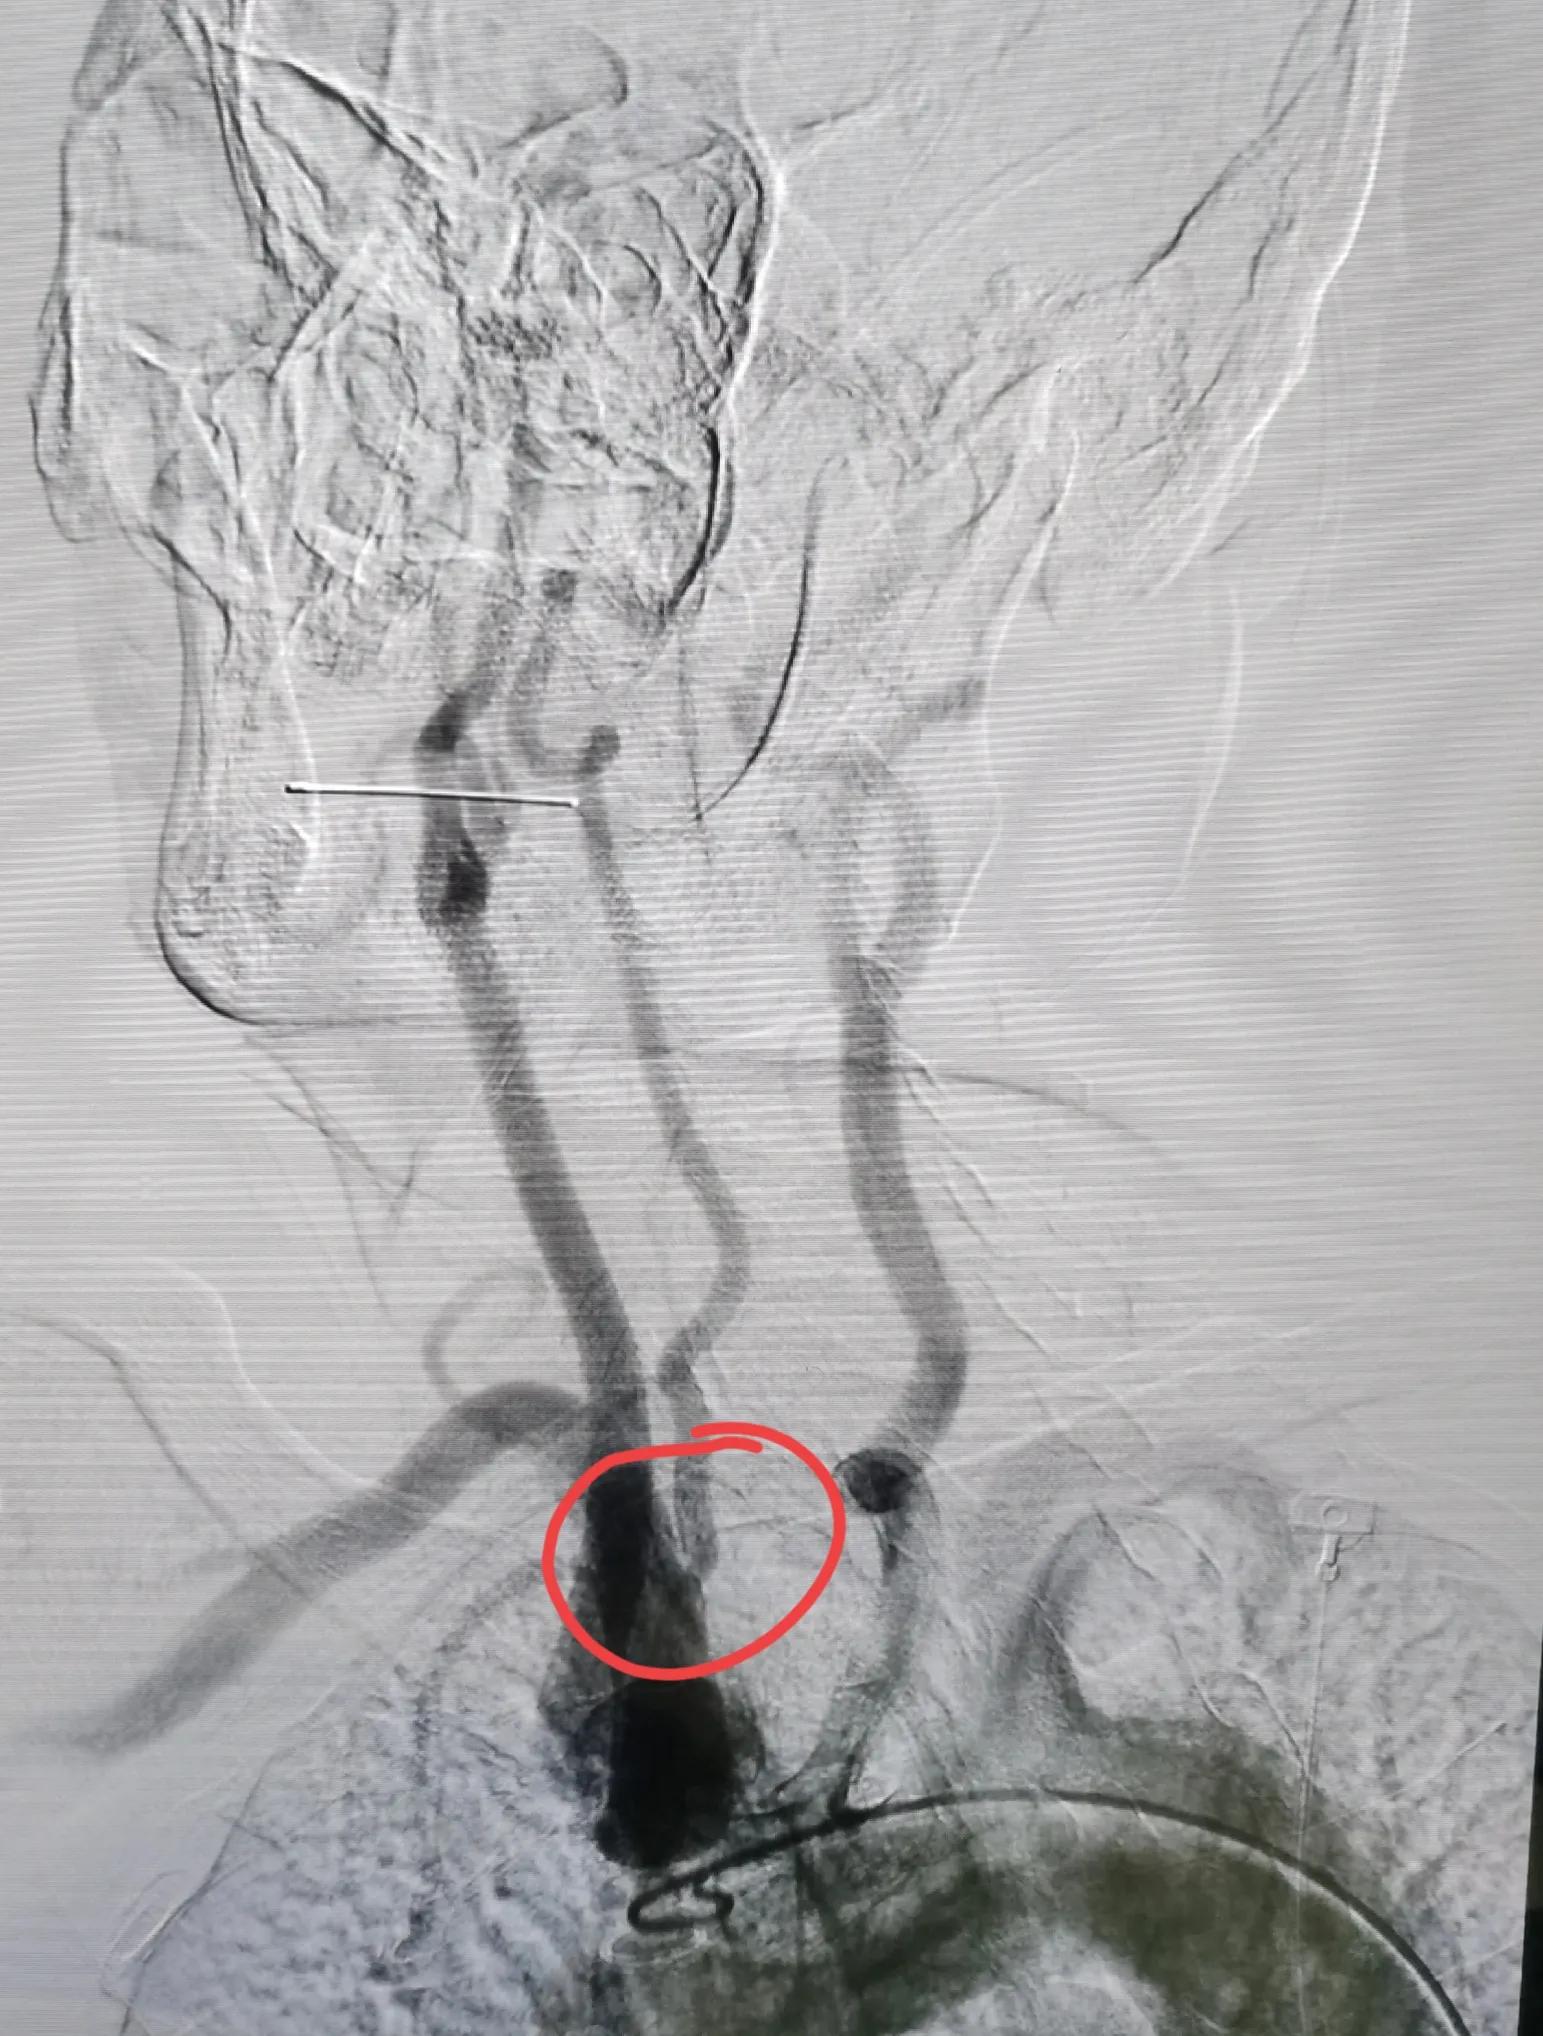

于是,次日,做了局麻下脑血管造影,可见:左侧椎动脉全程闭塞,仅仅在起始处见到一个残端,右侧椎动脉中度狭窄,

左侧椎动脉闭塞

右侧椎动脉中度狭窄